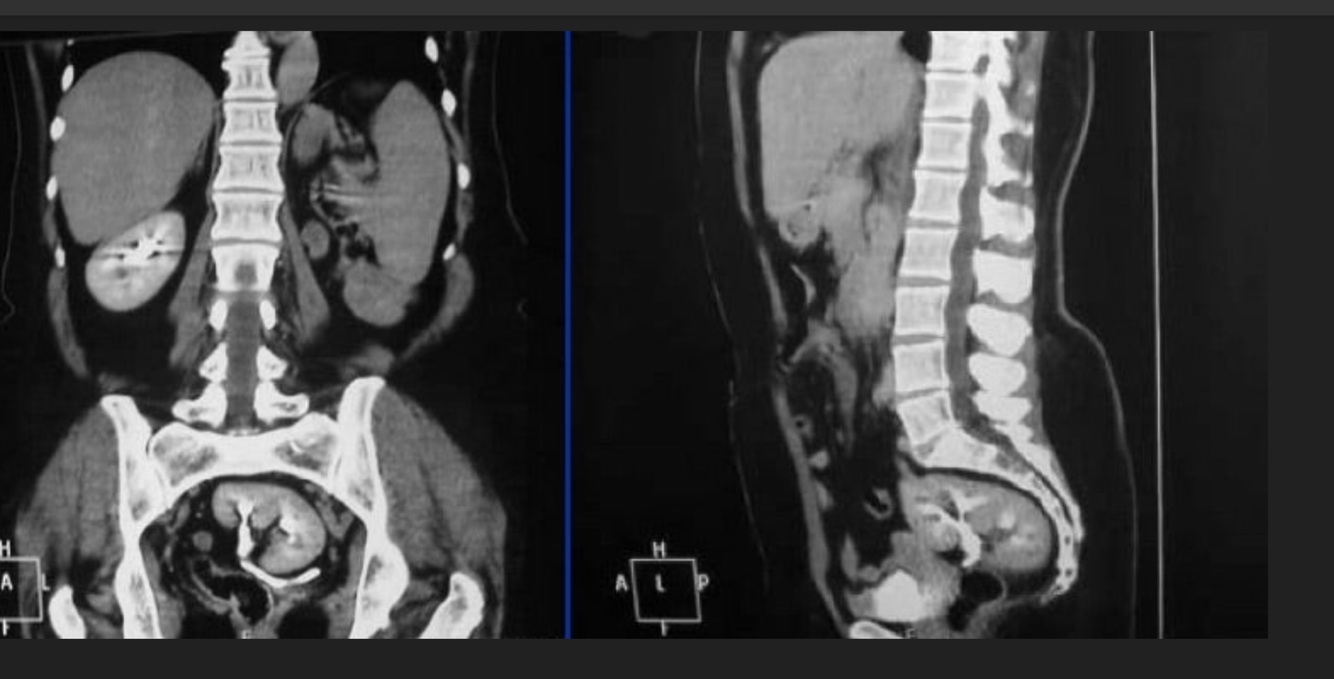

12

Q

-Hematuria silenciosa

-Astenia

-Adinamia

-Hiporexia

-Baja de peso de 12 kg

A

Cáncer renal